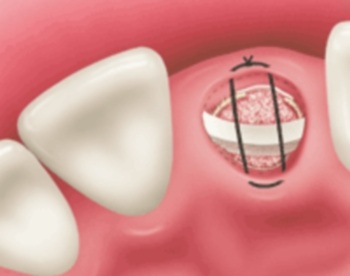

Hình 1a: Bác sĩ phẫu thuật để bộc lộ chân răng, và nhẹ nhàng lấy chân răng ra, không làm nứt hoặc bể xương ổ răng.

Hình 1b: Sau khi lấy chân răng ra, Bác sĩ sẽ ghép thêm xương nhân tạo ở phía dưới đáy ổ răng (nếu cần thiết).